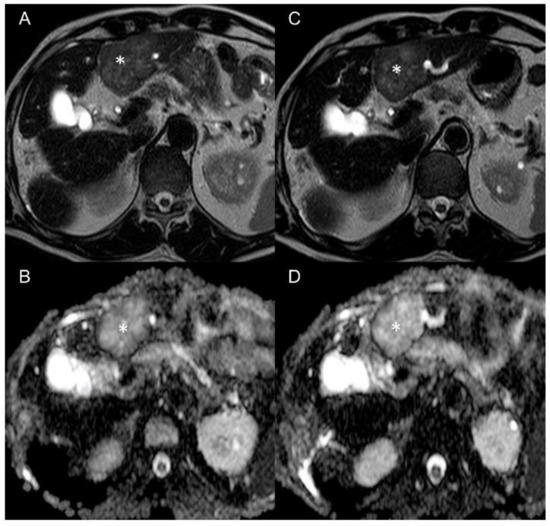

3.1. Imaging of Target Hit and Effectiveness